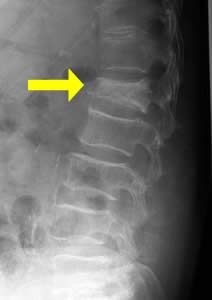

背骨のことを医学では「脊椎」と呼んでいます。脊椎圧迫骨折は、脊椎が押し潰されるように変形してしまう骨折です(図1)。

様々な原因で脊椎圧迫骨折は起こります。代表的な原因として、骨粗鬆症(こつそしょうしょう:骨のカルシウムが減る状態)、外傷、悪性腫瘍(がん)の転移、脊椎の良性腫瘍などがあります。

代表的な症状は、背中や腰の痛みです。体を動かす時に背骨の骨折に負担がかかり、痛みが発生します。骨折によって神経が押されたりすると、足の痺れなどが起こることもあります。全く症状が起こらない患者さんもいらっしゃいます。

(図1)脊椎圧迫骨折(矢印部分) 脊椎圧迫骨折に対するBKP治療とは